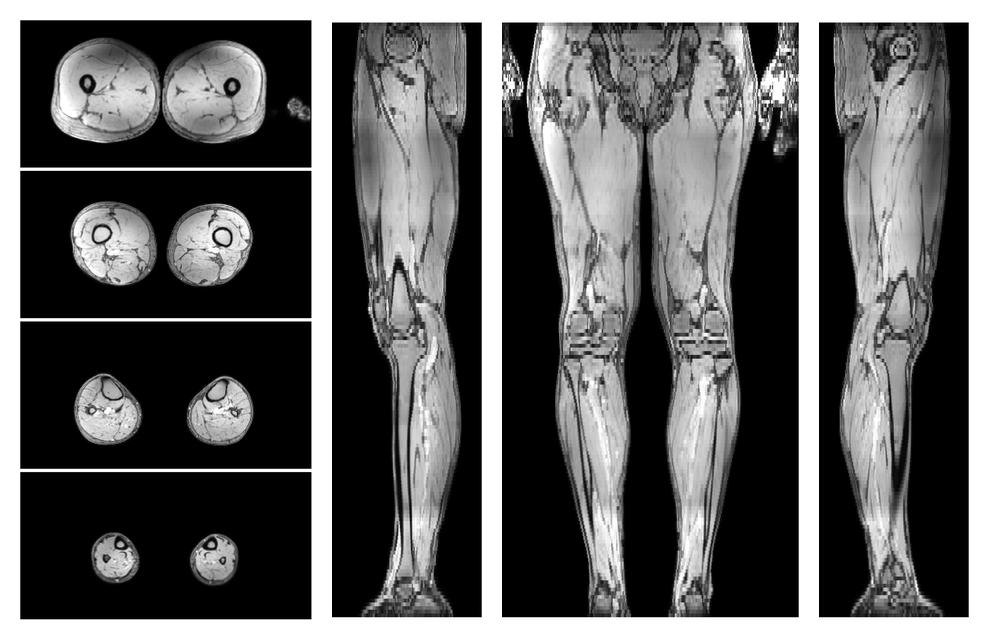

• Water only signal

The water part of the acquired multi-echo spin echo data.